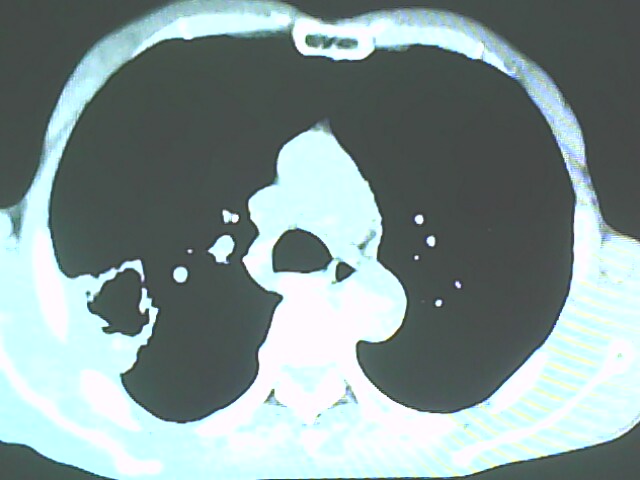

患者,男,66岁,以咳嗽、咳痰伴胸痛来就诊。

胸片提示右上肺占位病变。请各位老师看看ct。

请各位老师看看,考虑:癌性空洞吗?

考虑癌性空洞可能性大,空洞内壁不规则,病灶周围模糊,分叶、有毛刺

空洞内壁不规则,病灶周围模糊,分叶、毛刺呈日光放射状,突然截断,支持考虑癌性空洞

考虑右肺上叶后段周围型肺癌并癌性空洞形成。

考虑癌性空洞可能性大,内壁不规则,洞壁薄厚不均呈结节状突起,边缘模糊,分叶,毛刺

右上肺后段肺癌:

典型癌性空洞(偏心性,壁厚薄不均,内壁不光整),周围毛刺较僵硬,且有刺突征和血管聚集征